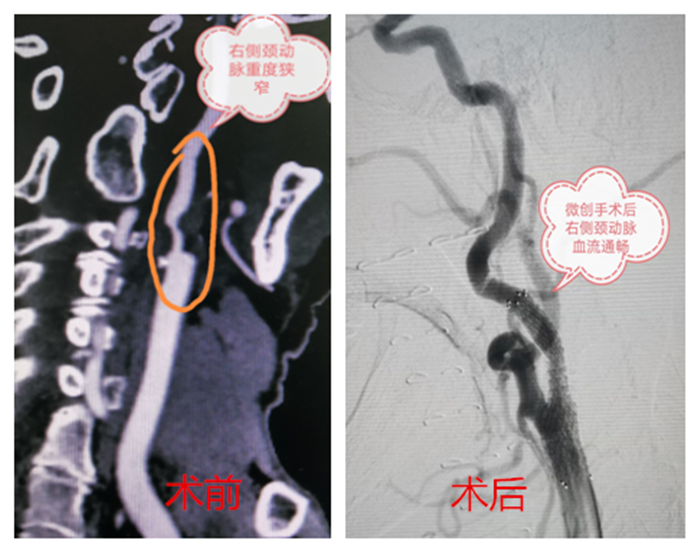

血管外科接診醫(yī)生程國(guó)兵仔細(xì)問(wèn)詢并完善相關(guān)檢查,經(jīng)頸動(dòng)脈CT血管成像提示:右頸內(nèi)動(dòng)脈起始段少量混合斑,管腔中重度狹窄。頭顱磁共振提示:右側(cè)急性腦梗。

在科主任陸煒的帶領(lǐng)下,血管外科診療團(tuán)隊(duì)為祝老先生行“超選擇性右頸動(dòng)脈造影+支架植入球囊擴(kuò)張術(shù)”。在非插管全麻下,穿刺右股動(dòng)脈,置入動(dòng)脈鞘,導(dǎo)絲通過(guò)動(dòng)脈鞘進(jìn)入右頸總動(dòng)脈,在右頸動(dòng)脈狹窄段遠(yuǎn)3厘米處放置保護(hù)傘導(dǎo)絲,沿著導(dǎo)絲放置球囊,用球囊壓力泵擴(kuò)張狹窄段,退出球囊后,在狹窄段成功置入支架。短短一個(gè)小時(shí),手術(shù)順利完成。

“太感謝你們了,老爺子‘任督二脈’打通,人都精神多了……”術(shù)后第二天,祝老先生就表示頭已經(jīng)不暈了,家屬深表感謝。